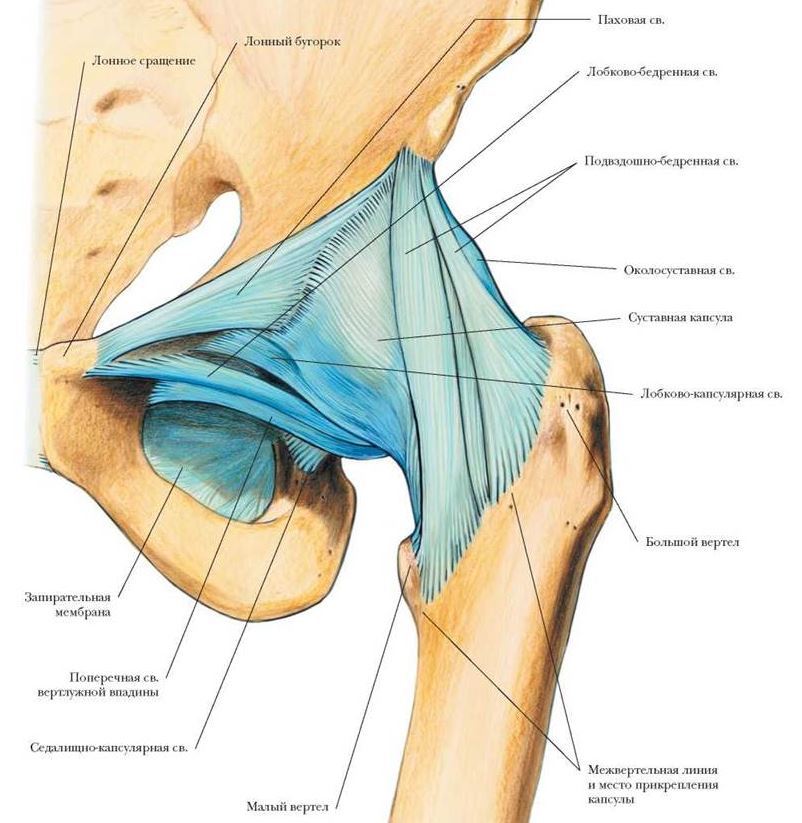

681594c727b2e_.JPG.b6882be91cdfffff6f1f71a8f9fddba4.JPG

Это считай повторная операция...

Сами импланты уже через час, на цементе, ни куда не денутся, вся реабилитация это в основном восстановление этой суставной сумки которая и держит сустав в комплекте....

А учитывая то что, не все люди в возрасте, могут чётко контролировать свои движения я и посоветовал не торопиться с активной физкультурой.....